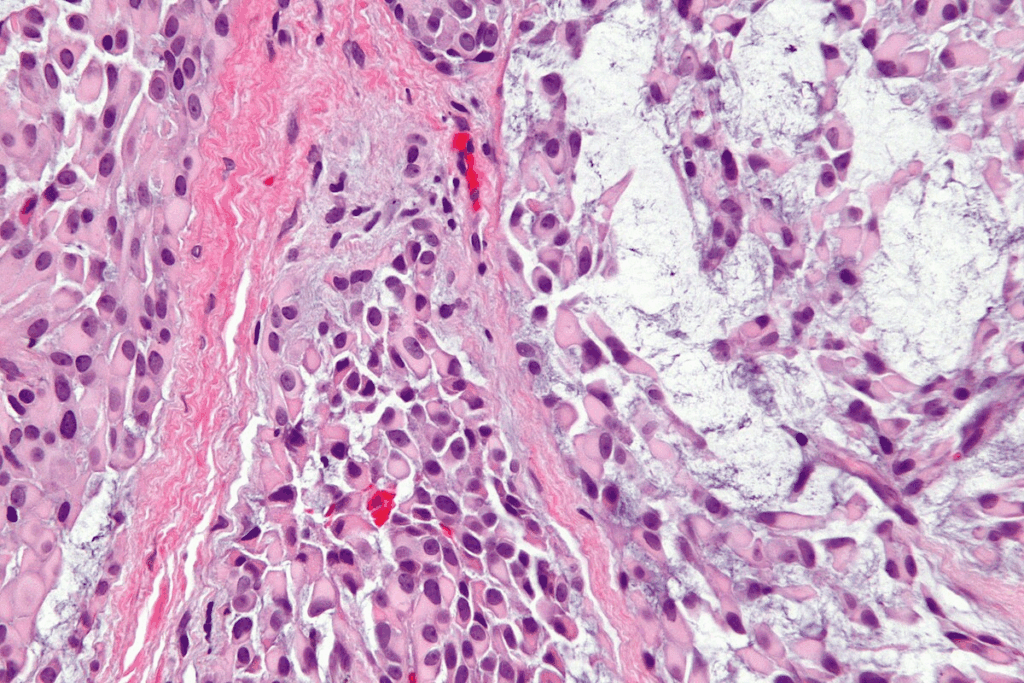

Distinguishing Cancerous from Normal Squamous Cells

Telling cancerous from normal squamous cells is tricky. It needs many tests. Cancer cells often look different, like irregular shapes or big nuclei. Tests like cytology and biopsy help spot cancer cells.